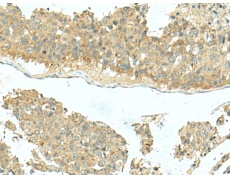

IHC positive control: